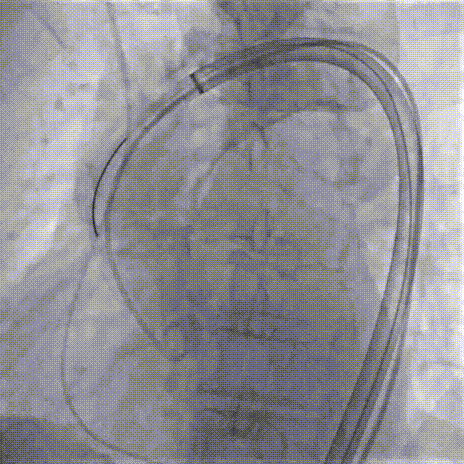

Step 8.最终造影:真实瓣环下方3mm标准位,完全同轴,轻微反流,猪尾撤出后反流完全消失

Step 9.CuspOverlap体位验证缘对缘对齐,挂钩位于最右方,基本避开冠脉开口

Step 10.验证器械同轴性,完全同轴